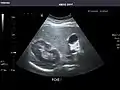

Abdominal ultrasonography (also called abdominal ultrasound imaging or abdominal sonography) is a form of medical ultrasonography (medical application of ultrasound technology) to visualise abdominal anatomical structures. It uses transmission and reflection of ultrasound waves to visualise internal organs through the abdominal wall (with the help of gel, which helps transmission of the sound waves). For this reason, the procedure is also called a transabdominal ultrasound, in contrast to endoscopic ultrasound, the latter combining ultrasound with endoscopy through visualize internal structures from within hollow organs.

Abdominal ultrasound can be used to diagnose abnormalities in various internal organs, such as the kidneys,[1] liver, gallbladder, pancreas, spleen and abdominal aorta. If Doppler ultrasonography is added, the blood flow inside blood vessels can be evaluated as well (for example, to look for renal artery stenosis). It is commonly used to examine the uterus and fetus during pregnancy; this is called obstetric ultrasonography.[2][3]